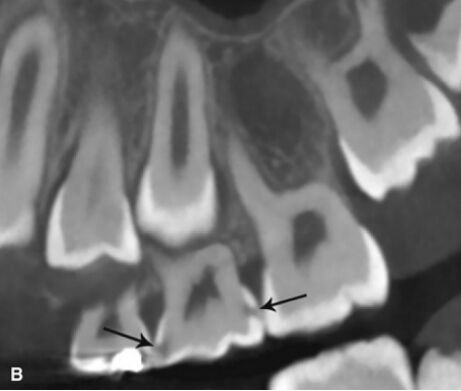

71.附圖之錐束電腦斷層掃描(cone beam computed tomography)片中,黑色箭頭所指牙齒異常為何? (A)咬耗(attrition) (B)磨耗(abrasion) (C)齲齒(dental caries) (D)內吸收(internal resorption)